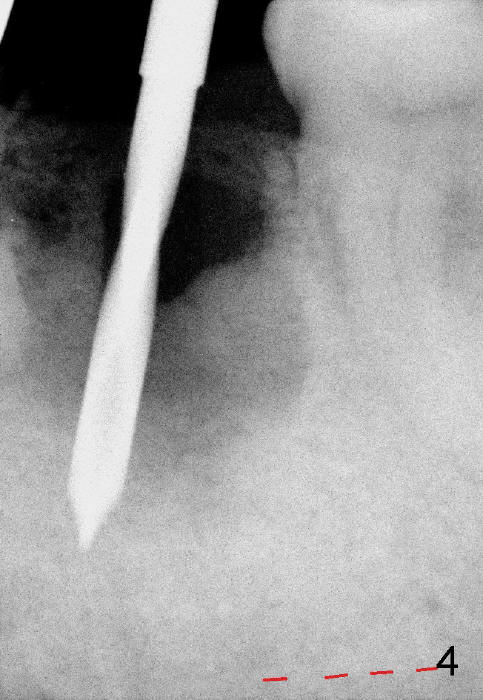

The initial trajectory using 2 mm pilot drill is off (Fig.4), whereas the 2nd one is good (Fig.5).